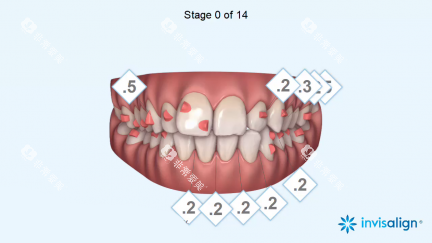

二、牙齿矫正项目

隐形矫正 | 17000起 |

说明:牙齿矫正项目提供多种选择,从传统的金属托槽矫正到隐形矫正,满足不同年龄段和需求的患者。隐形矫正技术如隐适美和时代天使,不仅美观,还方便患者日常生活。